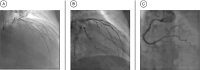

Background Cardiac myxoma is the most common primary cardiac tumor. Although benign, it can cause life-threatening complications due to embolization. Case Presentation We describe an ST-elevation myocardial infarction (STEMI) involving a giant right atrial myxoma and persisting foramen ovale (PFO) in a 64-year-old male patient and report on emergency percutaneous interventional therapy and subsequent cardiac surgery to remove the right atrial myxoma. Conclusion A right atrial myxoma, combined with a PFO, can cause a STEMI. Therefore, every acute coronary syndrome patient should undergo ultrafast exploratory emergency echocardiography to protect the physician from unpleasant surprises.